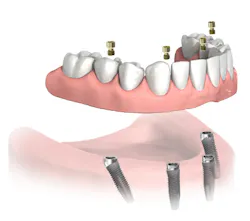

I removed the bridge to find the intaglio packed with food debris. The patient’s tissue was inflamed (figure 3), and she had developed a fungal infection. This could have been avoided with better presurgical preparation, adequate bone reduction, and proper vertical space development, which would have allowed the lab to make a hygienic intaglio (figure 4). Note the smooth and flowing intaglio surface in Figure 4. This is a bridge that can be easily maintained by the patient and hygienist.

Figure 4: Ideally convex intaglio surface for easy cleaning